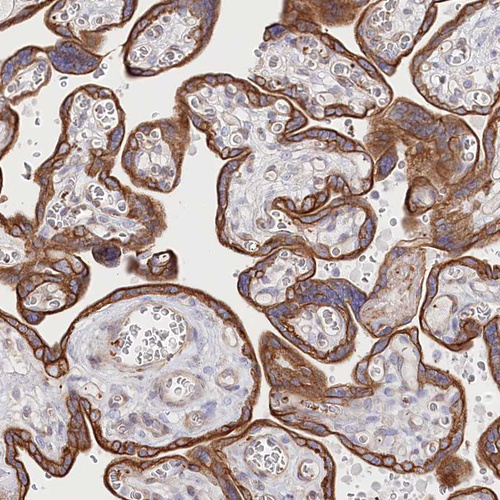

Immunohistochemical staining of human placenta shows strong membranous positivity in trophoblastic cells.